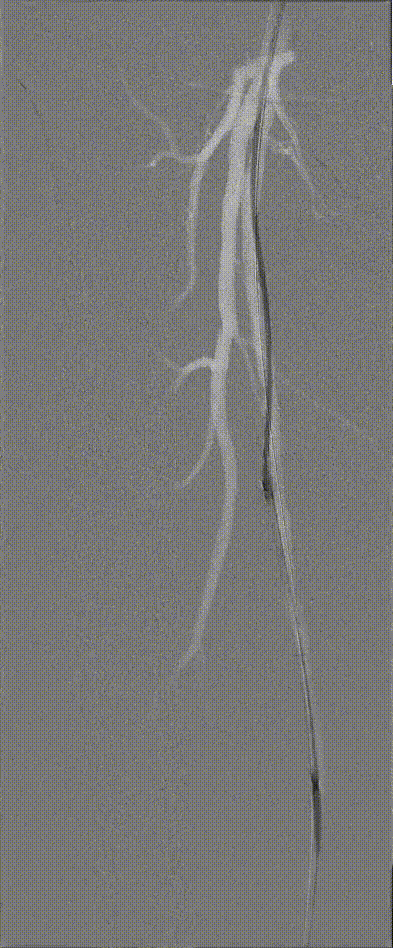

图:造影及通过病变

图:IVUS确认

图:Jetstream 应用

图:DCB 5-250 扩张及全程造影